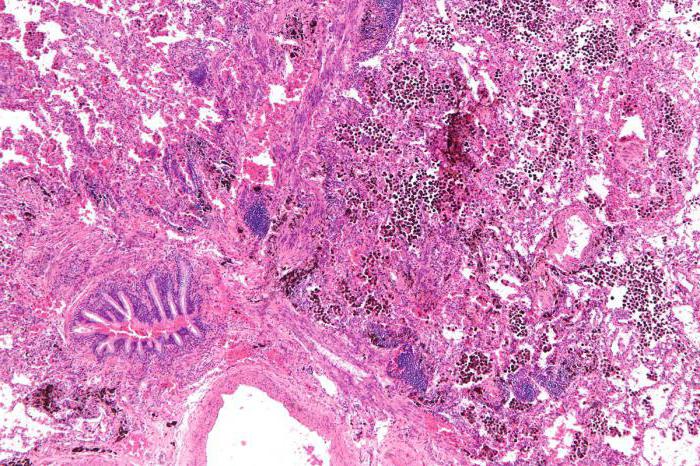

При туберкулезе легких кровохарканье может быть следствием токсического влияния микобактерии туберкулеза на стенки капиллярных сосудов, специфических изменений в сосудах легкого и патологического развития сосудов в фиброзно измененной легочной ткани.

Кровохарканье может происходить вследствие выхода из русла крови всех ингредиентов ее через неповрежденную стенку кровеносного сосуда (per diapedesin). Наиболее часто такое кровохарканье наблюдается при начальных формах туберкулеза, при свежих очаговых изменениях с перифокальной зоной вокруг, при инфильтратах и пневмонических фор мах туберкулеза, когда нет еще деструкции легочной ткани.

Такой же механизм кровохарканья может быть и при хронических, далеко зашедших формах легочного туберкуле в период обострения, если кровохарканье возникает из участков легкого, занятых перифокальным воспалением.

У больных фиброзно-кавернозным туберкулезом кровохарканья и легочные кровотечения большей частью возникают вследствие разрушения стенки кровеносного сосуда (per rexin). Развитие туберкулезного процесса в стенке кровеносного сосуда с последующим разрушением его вызывает обильное легочное кровотечение. Количество излившейся крови зависит от диаметра сосуда, быстроты образования и прочности тромба. Перфорация кровеносного сосуда, расположенного в стенке каверны, а иногда проходящего через каверну в виде трабекулы, вызывает часто обильное легочное кровотечение с последующей аспирацией крови в ниже лежащие отделы легкого или в противоположное легкое.

При старых цирротических формах туберкулеза в участках обширного и массивного развития соединительной ткани на месте воспалительного или деструктивного процесса происходят деформация кровеносных сосудов и образование капиллярных аневризм. Разрушение этих аневризматических образований может быть причиной частого кровохарканья. Хотя выделение крови в подобных случаях происходит per rexin, потеря крови при этом незначительна.